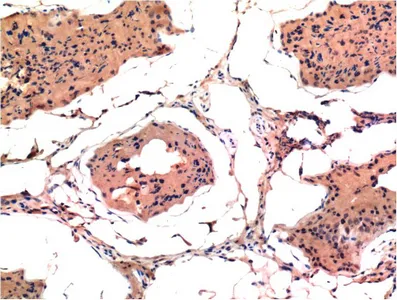

CDX2(14H6)Mouse Monoclonal Antibody

Cat: AMM08595

Size1:50μL Price1:$118

Size2:100μL Price2:$220

Size3:200μL Price3:$380

Application:WB,IF-P,IF-F,ICC/IF,IHC-P

Reactivity:Human,Mouse,Rat

Conjugate:Unconjugated

Optional conjugates: Biotin, FITC (free of charge). See other 26 conjugates.

Gene Name:CDX2